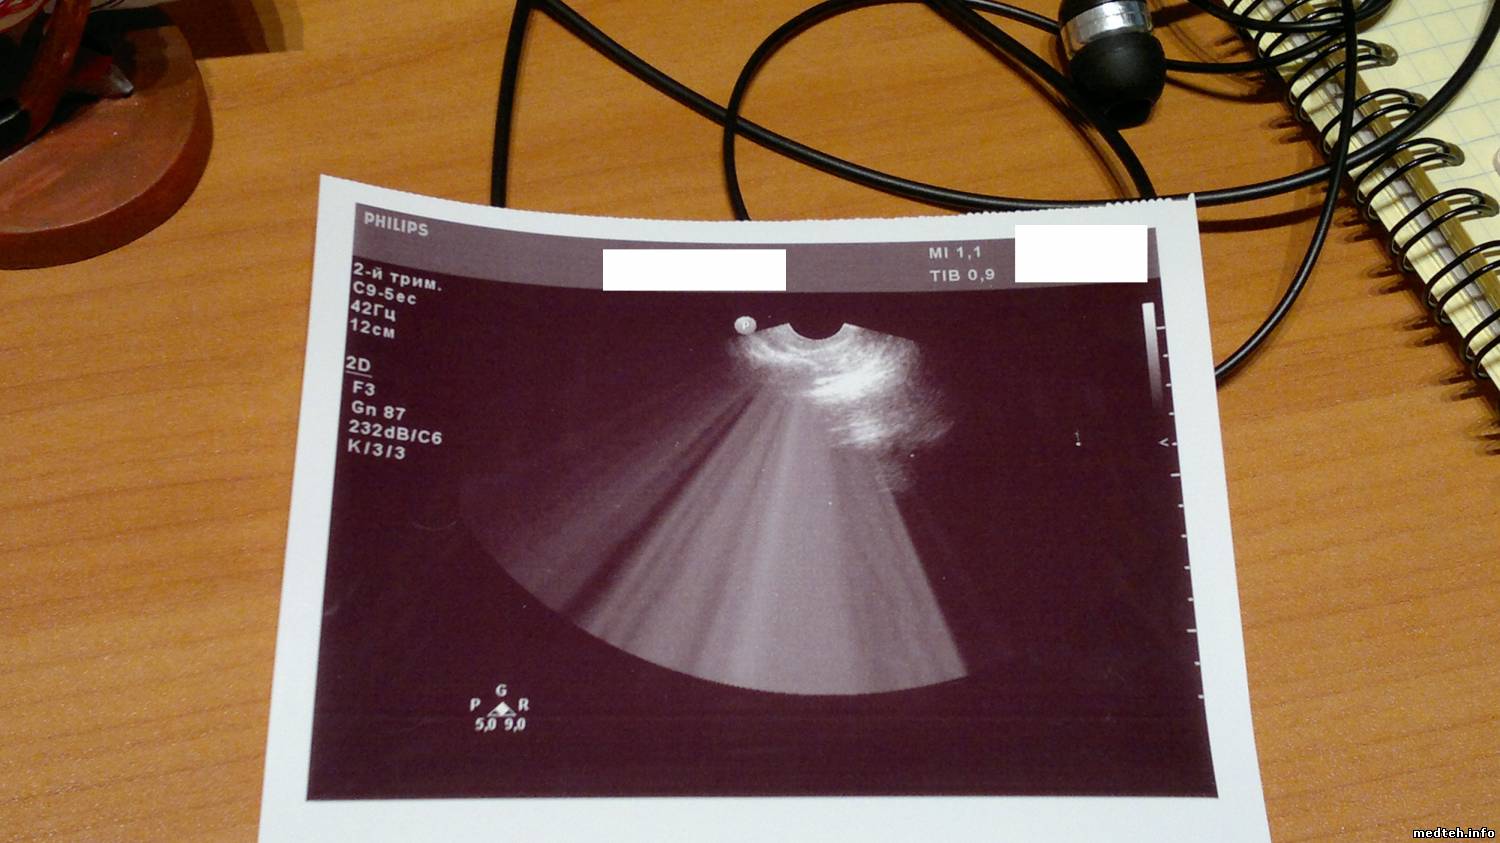

При тестировании аппарата выявились косяки с вагинальником и линекой-наложение серого фона/наводка(не знаю как обозвать), см. фото ниже.

Собственно нужно быть уверенным что дело в датчиках,а не в аппарате.Смущает симметричность наложиний серого на линейке. На вагинальнике нормально кажет только 1/5 часть всего сектора. Да, и к каждому датчику в упаковке шла распечатка с фантома-всё красиво и чётко. Вся упаковка цела, внешних/механических дефектов нет.

1367691.jpg (121.1 Kb) · 9129443.jpg (125.6 Kb) · 5411872.jpg (104.1 Kb)